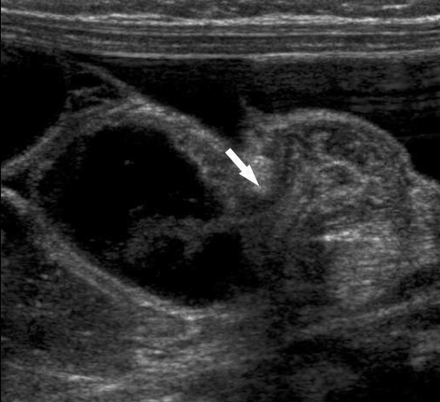

临界区左侧的部分小肠肠管塌陷(图2),看不到蠕动,表现为肠管的受压和堆积,好像被紧紧地填入一个囊内。

图2 过渡区左侧横向(A)和纵向(B)扫描显示肠管堆积成团并受压,好像在疝囊内紧紧的压在一起。